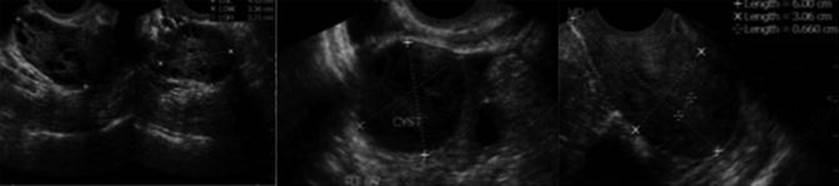

Monitoring Abnormal Response (Figs. 2.27, 2.28, and 2.29)

Fig. 2.27

Abnormal response to ovarian stimulation. (a) Premature luteinization, (b) LUF, (c) Poor response, (d) Hyper-response

Fig. 2.28

Ovarian hyperstimulation syndrome

Fig. 2.29

Functional and retention cyst

Ultrasound is also useful in monitoring abnormal response to ovulation induction, which includes premature luteinization, LUF, endogenous LH surge, poor response, hyperstimulation, presence of retention or functional cysts, and ovarian torsion.

Premature Luteinization (Fig. 2.27a)

Follicles <15 mm with echoes are seen and these correlate with high P4 levels in the follicular phase. A premature and suboptimal LH surge results in progesterone production but no ovulation, and oocyte maturation without follicular rupture. It is associated with poor quality oocytes and embryos with an out of phase endometrium thus, reducing the implantation rate.

Luteinized Unruptured Follicle (LUF) (Fig. 2.27b)

Luteinized unruptured follicle is diagnosed when the dominant follicle is still apparent 48 h after administration of hCG or LH surge. The size of the follicle may reach 34–36 mm and has thick walls and may have internal echoes. The endometrium is thick and echogenic with no fluid in the pouch of Douglas. It is due to insufficient strength of the LH surge to induce follicular rupture but sufficient to induce oocyte maturation.

Poor Response (Fig. 2.27c)

Poor response can be predicted by estimating the baseline AFC and ovarian volume (<3–4 AFCs and volume <3 mL). At times, the AFC may be normal but the women may not respond to gonadotropins for various reasons, so the presence of less than two to three follicles on ultrasound on day 7 of ovulation induction with gonadotropins also suggests poor response.

Ovarian Hyperstimulation Syndrome (OHSS) (Figs. 2.27d and 2.28)

Ultrasound is essential for the prevention, diagnosis, and monitoring of OHSS. Judicial use of TVS for follicular monitoring while inducing ovulation with gonadotropins remains critical for the prevention of OHSS. TVS is also used to monitor the ovarian volume, keep record of number of follicles and corpus luteum and their size, diagnose ascites and pleural effusion when monitoring for the progress of OHSS. Ultrasound can also be used to guide paracentesis of the ascites or pleural effusion in cases, which develop severe respiratory distress to avoid trauma to ovaries or other abdominal structures.

Functional Cyst (Fig. 2.29)

Functional cyst is diagnosed by the presence of cyst at prestimulation baseline scan on day 2 or 3 of the menstrual cycles following GnRH agonist stimulation for downregulation. It is characterized by sharp edges and anechogenic contents and is due to the initial FSH surge, which occurs after commencement of GnRH agonist in a long downregulation cycle. The presence of a functional cyst requires either cancellation of cycle or an ultrasound-guided aspiration of the cyst before commencing ovulation induction.

Persistent/Retention Cyst (Fig. 2.29)

The presence of cyst at baseline scan suggests a follicle from previous cycle or a persistent corpus luteum. It may result due to growth of the smaller follicles following the hCG trigger. No drugs are administered for ovulation induction in the presence of a retention cyst. It is followed ultrasonographically and if persistent may require medical or surgical treatment.